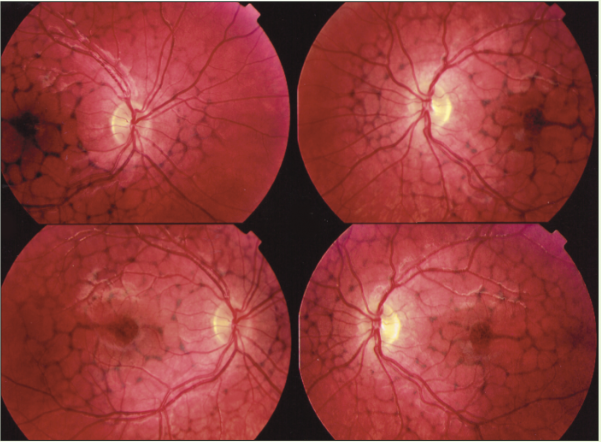

Mac tel 2 findings (Slide 14-17)

parafoveal grey/green; retinal thinning and decrease melanin

telangiectasia in fundus; vessels go into macula and bend at 90 degrees

crystalline deposits (damaged Muller cells); effects outer and inner layers

hyperplasia of pigment

Case 7 posterior exam

macula: absence of foveal reflex with pigment clumping OU

strange changes in macula

was told pt had aging changes; but our pt is 47 (too young for AMD)